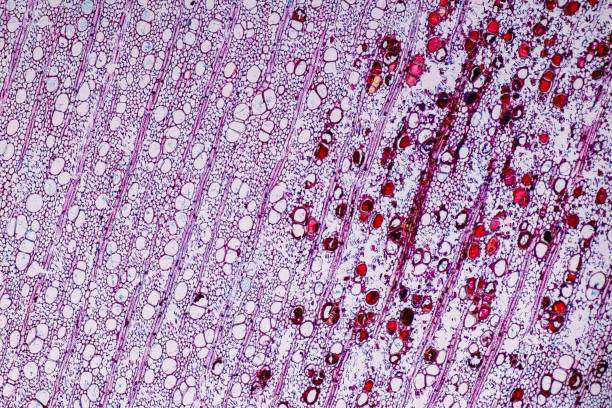

間充質干細胞(MSC)已顯示出通過促進受損肺組織修復來幫助治療慢性阻塞性肺病(COPD)的潛力。間充質干細胞被發現具有抗炎和免疫調節特性,有助于緩解慢性阻塞性肺病的氣道炎癥和肺氣腫[3]。在一項涉及人類脂肪源間充質干細胞(hADSC) 的研究中,發現這些細胞通過稱為間充質-上皮轉化的過程分化為肺泡上皮細胞,從而改善了慢性阻塞性肺病的發病機制。

另一項涉及間充質干細胞(ADMSC)的研究證明了自體支氣管內或靜脈輸注MSC對COPD患者的安全性和可行性。雖然這些研究顯示了使用間充質干細胞治療慢性阻塞性肺病的前景,但值得注意的是,它們的重點是控制癥狀和改善患者的生活質量,而不是提供疾病的治愈方法。需要進一步的研究和臨床試驗來充分了解間充質干細胞在慢性阻塞性肺病治療中的潛力,并開發基于這些細胞的有效療法。

干細胞是未分化的細胞,具有自我更新和分化成各種細胞類型的能力。在慢性阻塞性肺病的背景下,干細胞有可能分化成肺特異性細胞類型,包括支氣管和肺泡細胞,并促進組織修復和再生。

慢性阻塞性肺病的干細胞療法涉及通過靜脈輸注或直接注射將外源干細胞注入肺部。這些干細胞能夠歸巢到受損的肺組織、移植并分化成功能性肺細胞。此外,它們還釋放各種生長因子和抗炎分子,促進組織愈合并減少肺部炎癥。